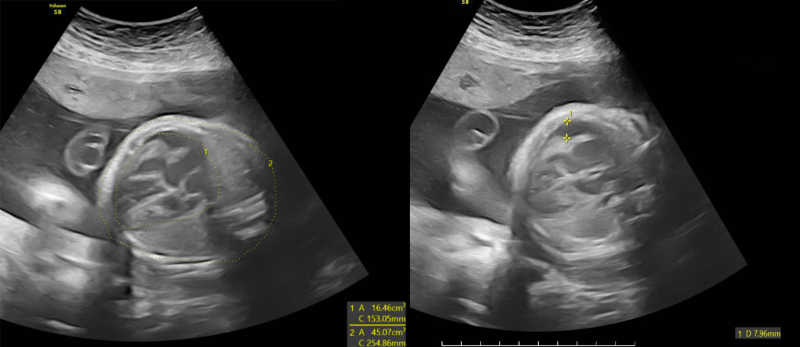

Thai nhi dị tật nặng, hàng loạt bất thường được phát hiện trên siêu âm

Tại đây, với thiết bị siêu âm hiện đại và đội ngũ bác sĩ chuyên môn cao, các dấu hiệu bất thường được kiểm tra, xác nhận chi tiết, bao gồm:

- Tim to kèm dịch màng ngoài tim: Hình ảnh tim lớn bất thường với dịch quanh tim, cảnh báo nguy cơ suy tim hoặc rối loạn tuần hoàn;

- Gan và lách to: Quan sát trên siêu âm cho thấy cả gan và lách đều lớn hơn mức bình thường, biểu hiện tình trạng viêm hoặc rối loạn chức năng các cơ quan này;

- Giãn não thất hai bên và giãn hố sau: Hình ảnh giãn não thất hai bên rõ rệt, kèm giãn hố sau, là dấu hiệu tổn thương não nghiêm trọng, có nguy cơ gây chậm phát triển trí tuệ, động kinh hoặc các biến chứng thần kinh sau sinh.

Các bất thường ở thai nhi được phát hiện trên hình ảnh siêu âm

Những hình ảnh siêu âm này phản ánh mức độ nghiêm trọng của tình trạng nhiễm trùng thai nhi. Ngay sau khi thực hiện siêu âm, BSCKI. Trần Thế Quỳnh - Chuyên khoa Chẩn đoán hình ảnh, Phòng khám Đa khoa MEDLATEC Thanh Xuân - người trực tiếp thực hiện siêu âm trường hợp này đã thông báo chi tiết cho thai phụ về các bất thường, giải thích ý nghĩa của từng hình ảnh. Đây là những dấu hiệu tiên lượng nặng có thể gây nhiều biến chứng cho thai như bại não, điếc bẩm sinh... Kết quả hội chẩn cùng các bác sĩ tuyến trên, chị P. có chỉ định đình chỉ thai kỳ do tiên lượng xấu.